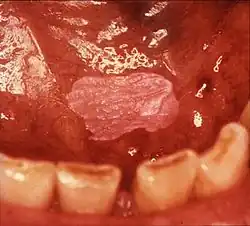

Leukoplakia of the soft palate

Homogeneous leukoplakia in the floor of the mouth in a smoker. Biopsy showed hyperkeratosis

Sometimes leukoplakia of the floor of mouth or under the tongue is called sublingual keratosis,.[19] though this is not universally accepted to be a distinct clinical entity from idiopathic leukoplakia generally,[19] as it is distinguished from the latter by location only.[3] Usually sublingual keratoses are bilateral and possess a parallel-corrugated, wrinkled surface texture described as "ebbing tide".[3]